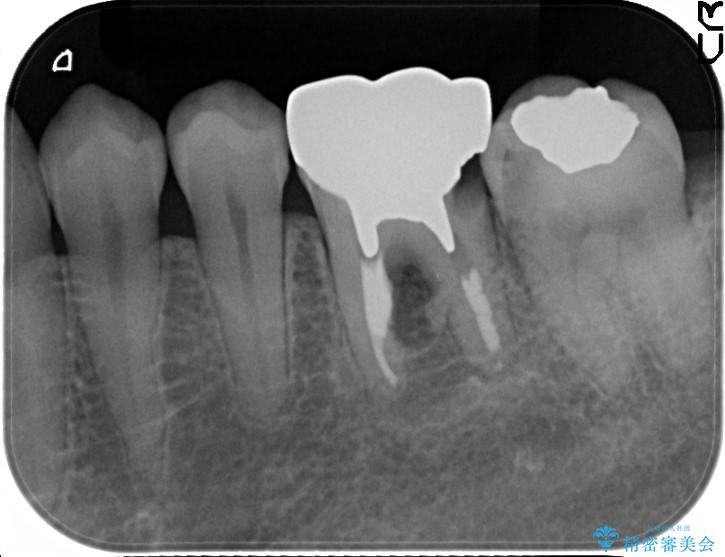

食べ物を噛んだ時に歯がしみる、ズキズキ痛む、長引く痛み。不可逆性歯髄炎の治療

食事の際に歯がしみてしまう、また最近になって何もしていないのにズキズキ痛んだり長引いている痛みがある、とのことで来院されました。